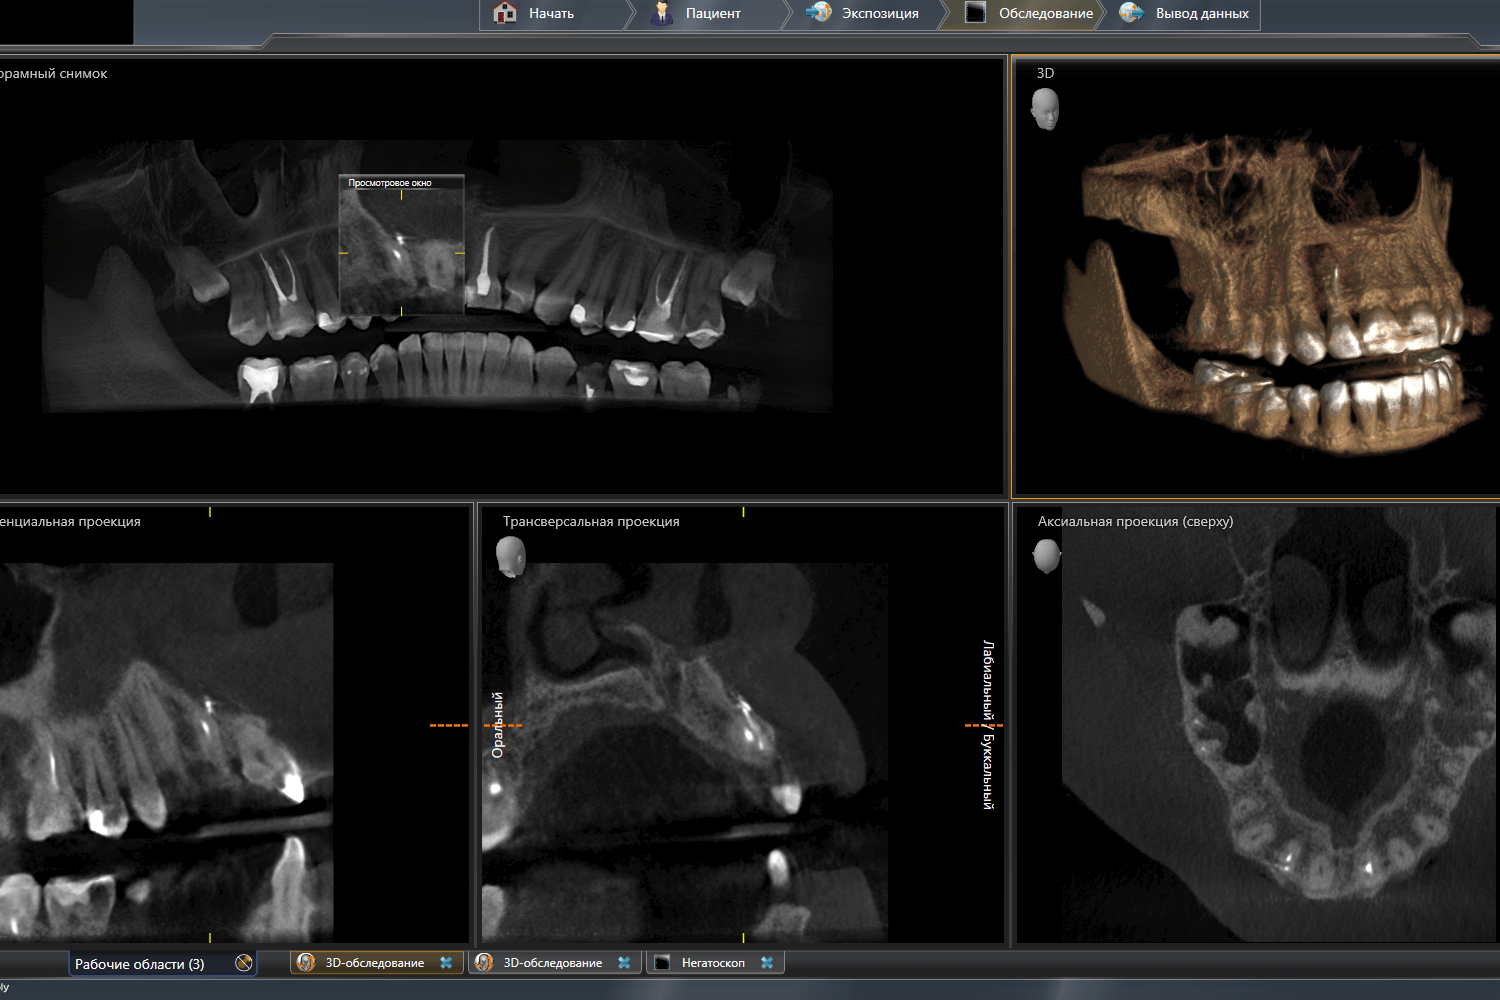

После КТ-исследования мы увидели 2 "перфорации" на корне зуба 1.2. с выходом свищевого хода на дёсны. Для того чтобы сохранить объём кости в эстетически значимой зоне, было принято решение удалить зуб и установить имплантат с временной коронкой.

КТ-исследование